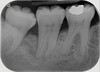

Vertical root fracture on X-ray – diagnosis?

• Fractura verticalis radicis dentis (vertical root fracture).

• Treatment: Extraction